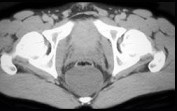

- 单项选择题男,21岁, 下腹部一囊性肿块,无压痛, 请结合图像,选择最可能诊断  (    )

- A、盆腔脓肿

- B、结肠重复畸形囊肿

- C、神经纤维瘤

- D、神经鞘瘤

- E、间质瘤